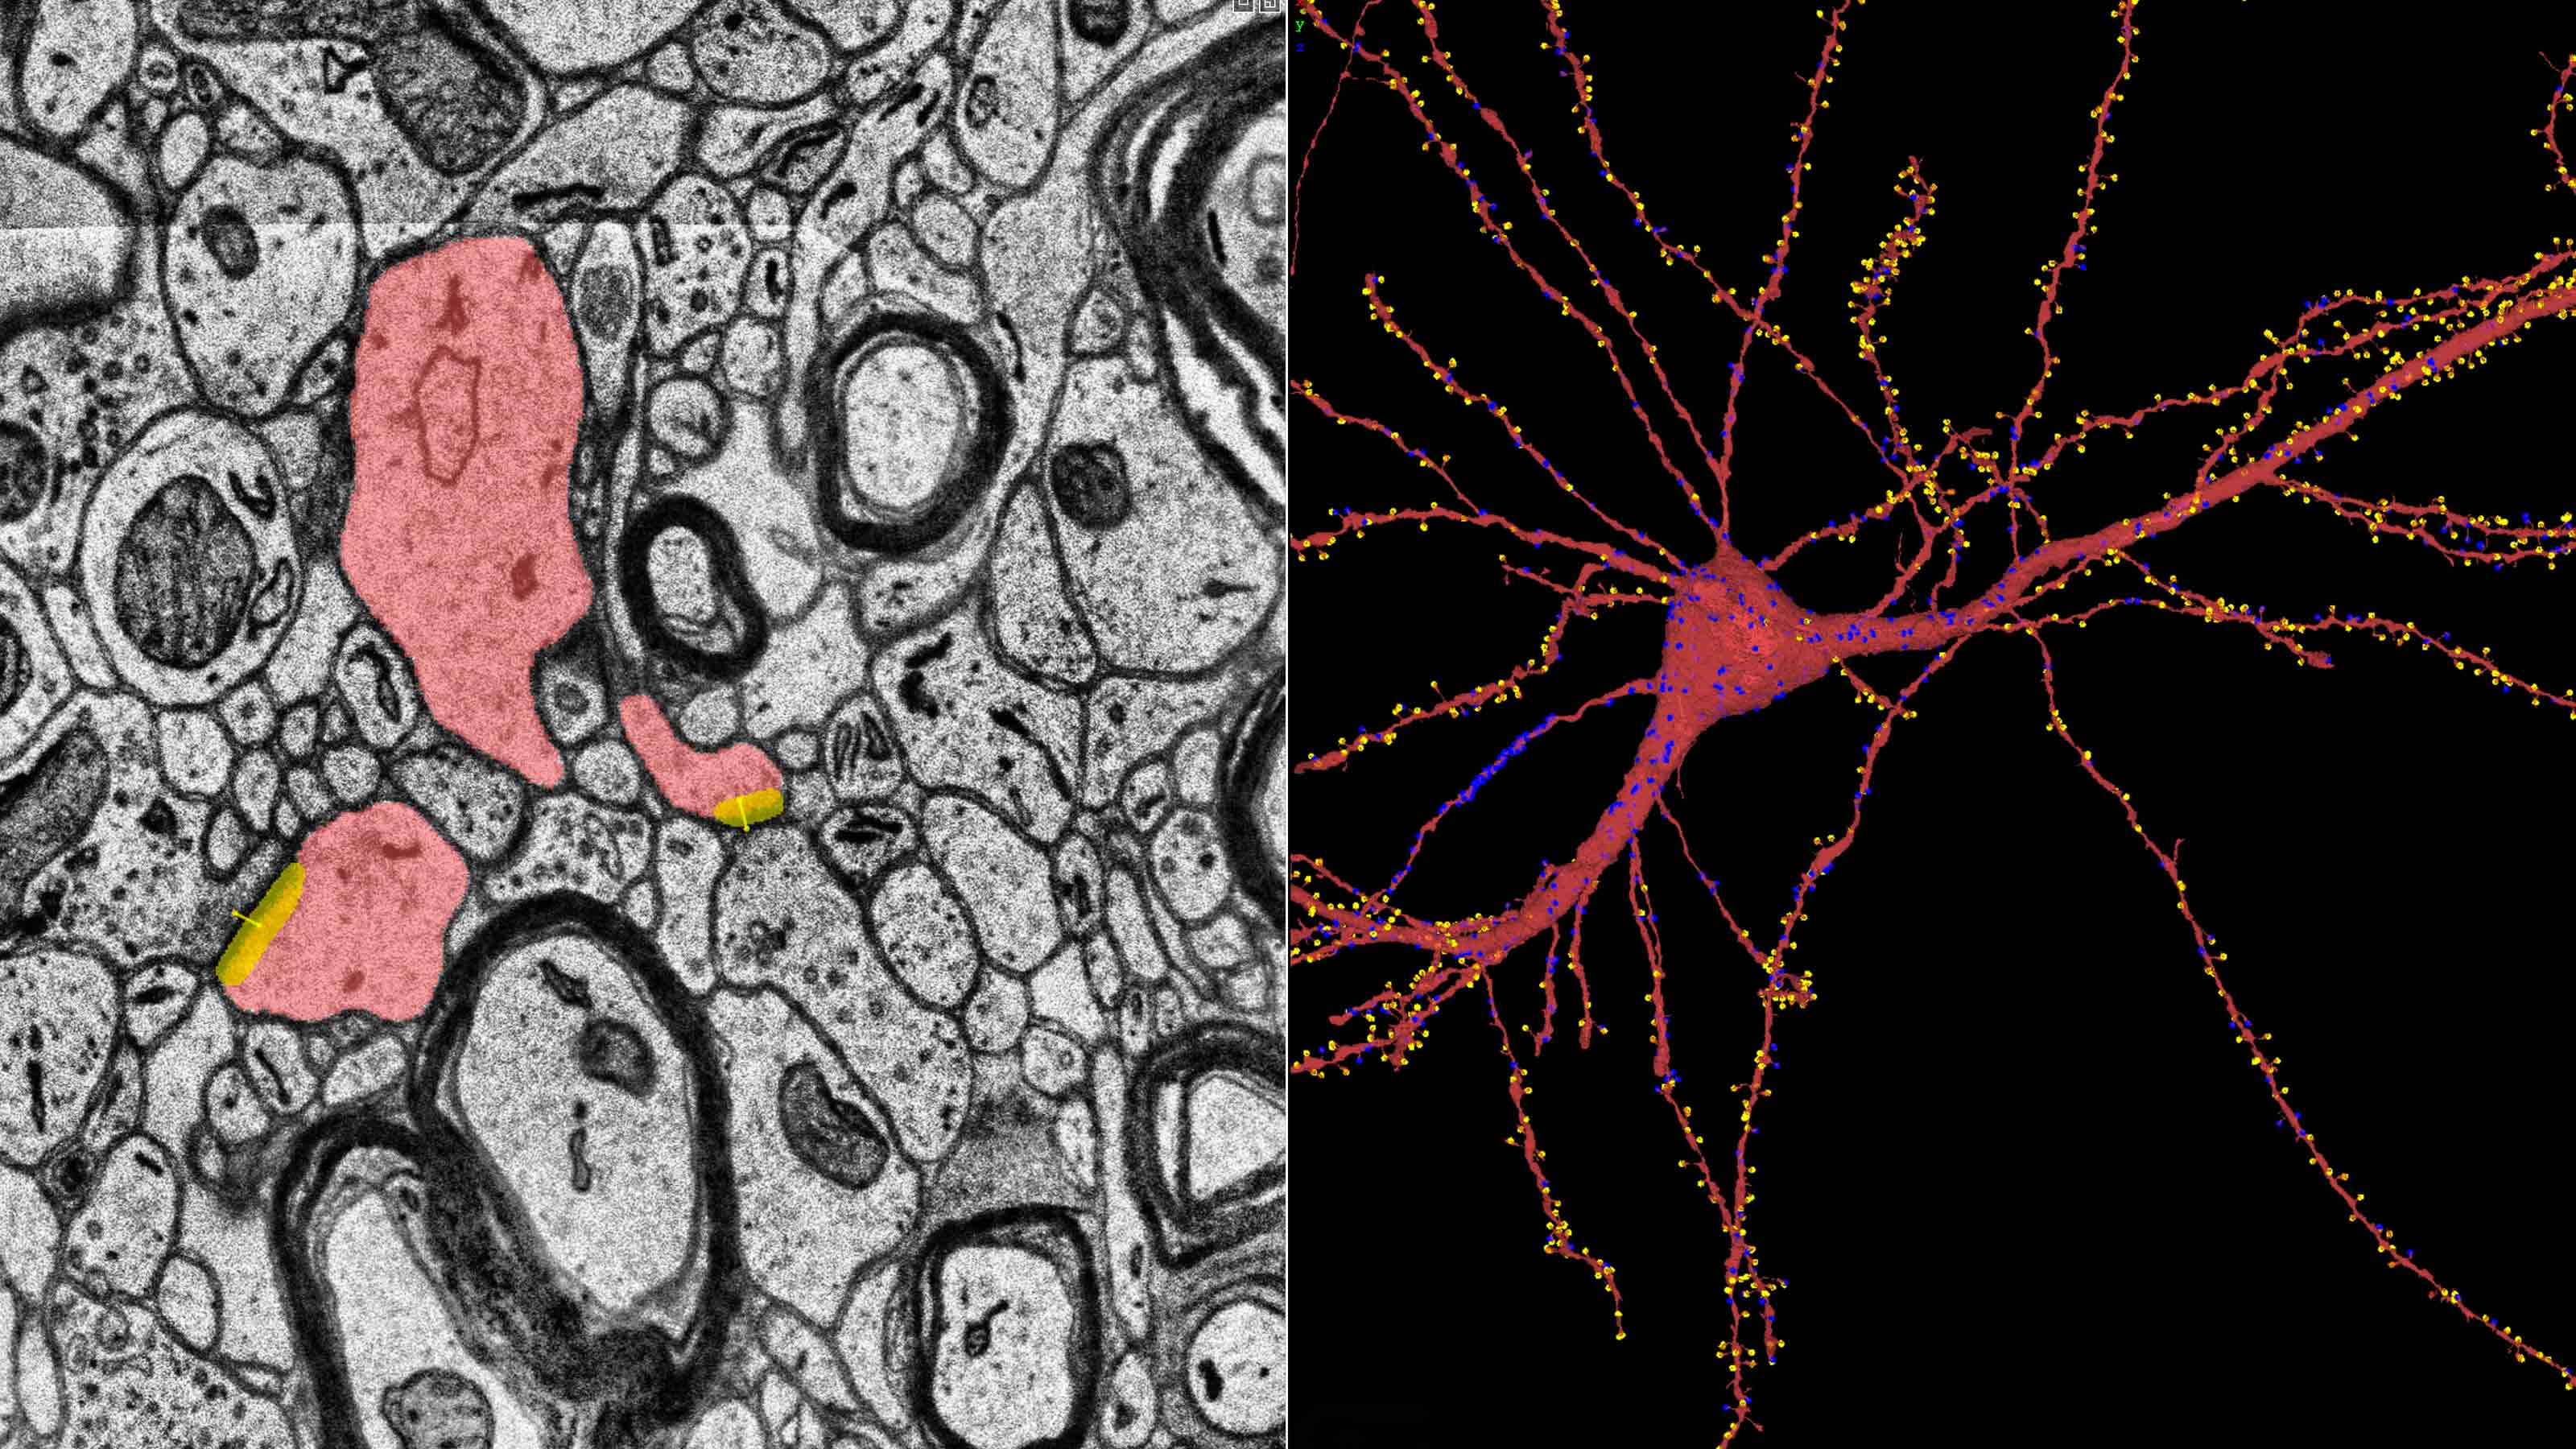

Google and Harvard have created the most detailed brain map yet